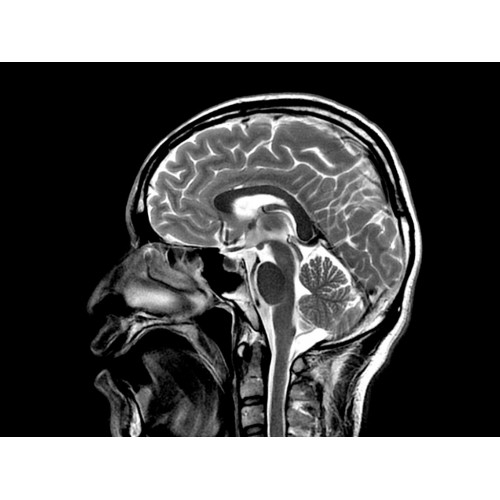

МР-томограф Optima MR450w позволяет получать изображения исключительно высокого качества, которые помогают установить диагноз. Чтобы удовлетворить ожидания клиентов в отношении высокого качества, в МР-томографе Optima MR450w были сохранены дополнительные возможности платформы Discoverу, привнесшие в его работу универсальность и мощь.

• Магнит переработанной конструкции — полностью новый магнит длиной 145 см обеспечивает однородную контрастность тканей в удобных для пациента условиях.

• Цифровой РЧ-приемник OpTix — эксклюзивная оптическая РЧ-система увеличивает четкость сигнала и его интенсивность, формируя чистые и резкие изображения.